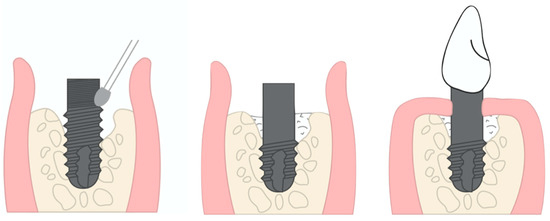

1. Introduction